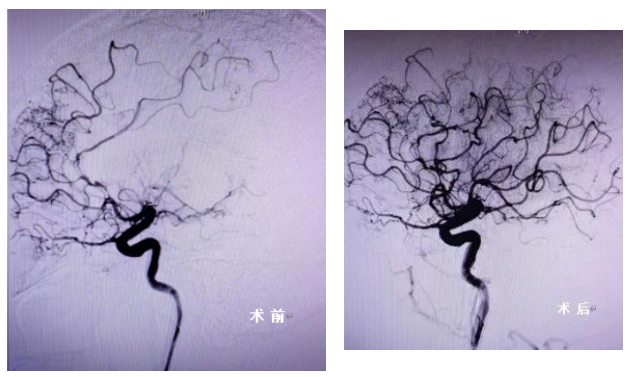

许老师到医院时,已经超过了静脉溶栓的4.5小时的时间窗,再不及时治疗就会留下偏瘫等后遗症。好在经神经介入团队评估后,认为许老师的核心梗死区与缺血半暗带区不匹配,这意味着,及时开通血管就可挽救较大范围的半暗带,达到功能恢复。

▲术前(左)、术后(右)影像对比图

随后,神经介入医生们、导管室护士迅速到位,许老师也立即被送往介入导管室接受手术。术中造影印证了术前判断,是左侧大脑中动脉闭塞,再结合病史和发病特点,考虑血管狭窄基础上急性血栓形成。随后,在微导丝引导下,到达闭塞段成功取栓,将狭窄的原貌暴露出来,并小心翼翼地将球囊扩张,血管成功开通!